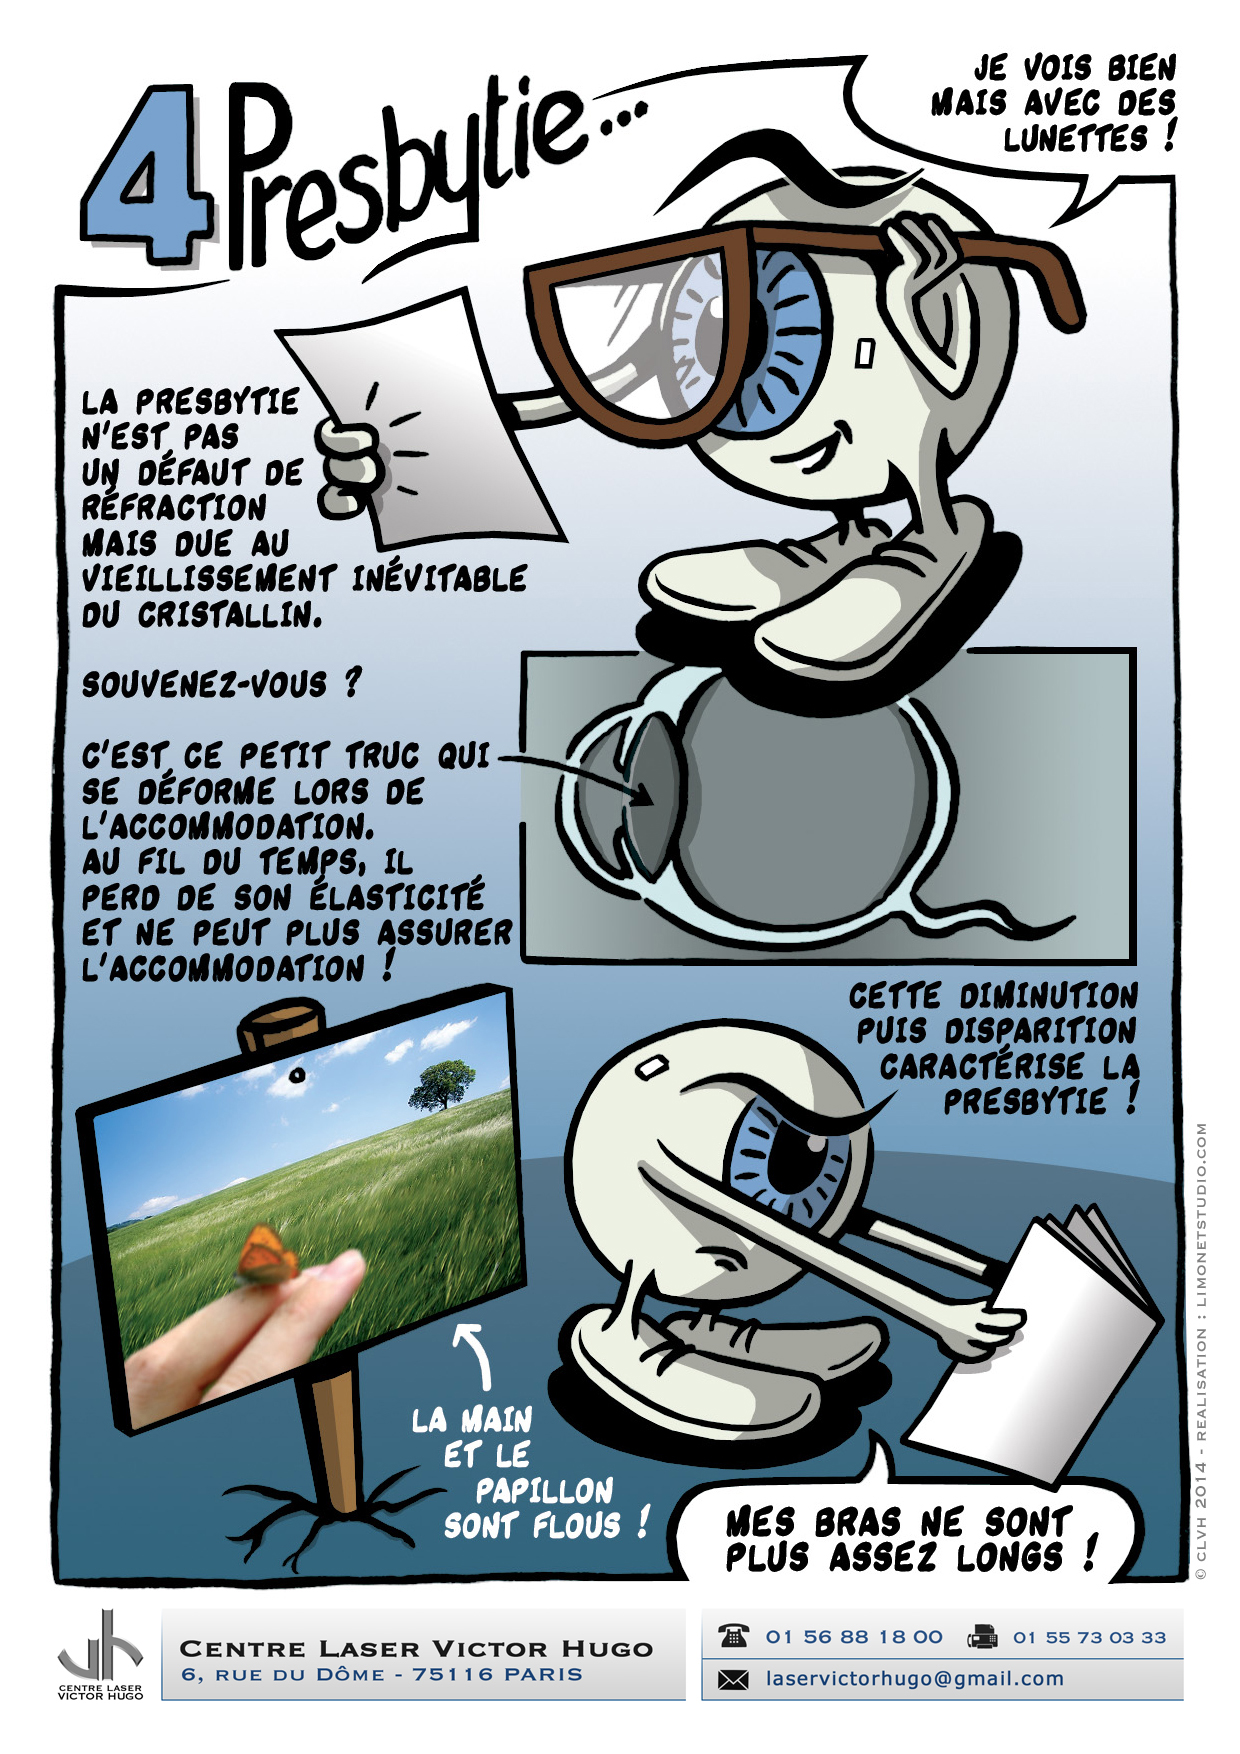

Afin de répondre aux interrogations d'un public de plus en plus intéressé, nous vous proposons cet ouvrage explicatif sous la forme d'une bande dessinée ludique. Cette bédé aborde les troubles de la vision, la chirurgie réfractive (LASIK, PKR et PresbyLASIK), la technique des anneaux et des implants. Cette bébé aborde également l'amblyopie et son traitement orthoptique. Maintenant... à vous de voir !